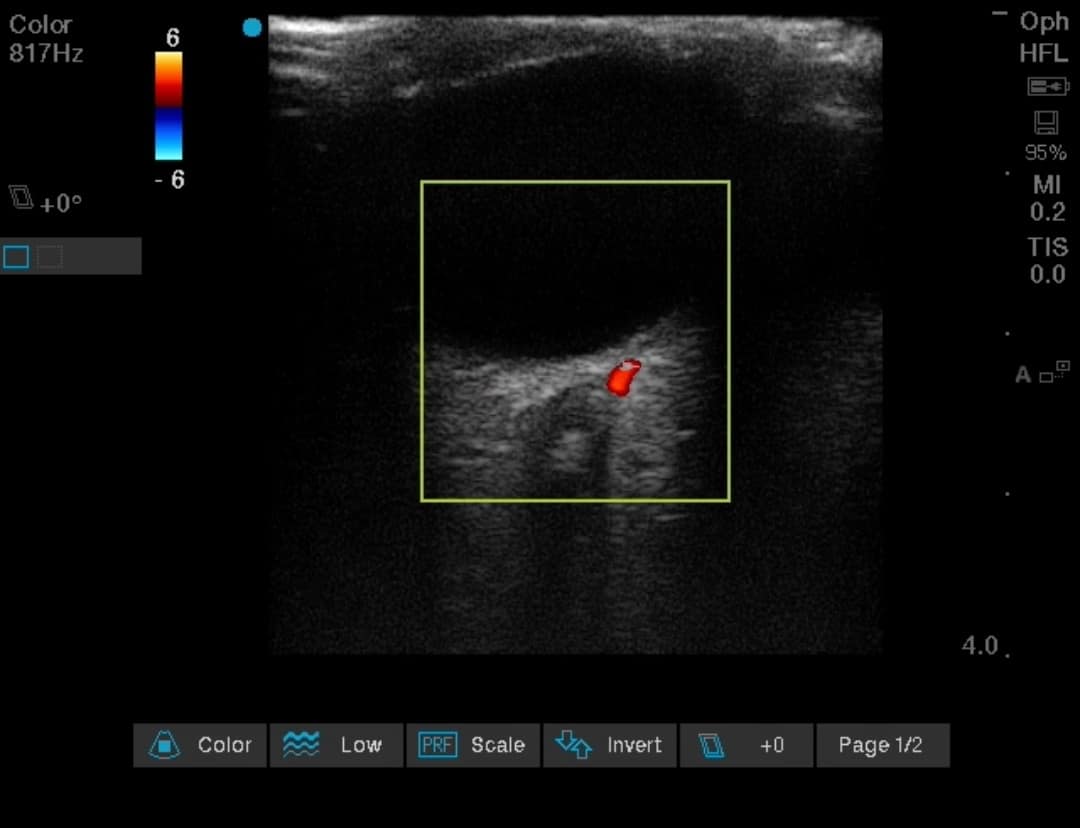

Ultrasound examination of the eye can help to diagnose CRAO in cases of a sudden blurring or loss of vision, eg, after major spine surgery, long duration prone position ventilation in ARDS patients, or intubated patients with COVID-19, etc.

It is observed as a hyper-echoic spot (ditzel) in the center of the optic nerve (retro-bulbar spot sign). This hyper-echogenic spot represents thrombosis of the central retinal artery.37 Retinal blood flow occlusion can be confirmed with use of color doppler (Figure 6 and Video 1), the accuracy of which itself depends upon the angle of insonation of the ultrasound beam.

A false positive assessment can be made in case of optic nerve drusen, which is a calcific material deposit in the head of the optic nerve/retina and presents clinically as blurring or loss of vision. Ocular ultrasound provides high specificity but low sensitivity to confirm diagnosis of CRAO.